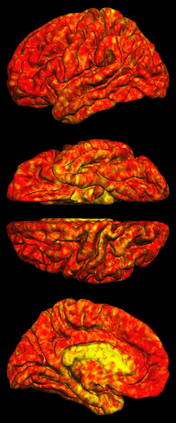

Due to various physical degradation factors and limited counts received, PET image quality needs further improvements. The denoising diffusion probabilistic models (DDPM) are distribution learning-based models, which try to transform a normal distribution into a specific data distribution based on iterative refinements. In this work, we proposed and evaluated different DDPM-based methods for PET image denoising. Under the DDPM framework, one way to perform PET image denoising is to provide the PET image and/or the prior image as the network input. Another way is to supply the prior image as the input with the PET image included in the refinement steps, which can fit for scenarios of different noise levels. 120 18F-FDG datasets and 140 18F-MK-6240 datasets were utilized to evaluate the proposed DDPM-based methods. Quantification show that the DDPM-based frameworks with PET information included can generate better results than the nonlocal mean and Unet-based denoising methods. Adding additional MR prior in the model can help achieve better performance and further reduce the uncertainty during image denoising. Solely relying on MR prior while ignoring the PET information can result in large bias. Regional and surface quantification shows that employing MR prior as the network input while embedding PET image as a data-consistency constraint during inference can achieve the best performance. In summary, DDPM-based PET image denoising is a flexible framework, which can efficiently utilize prior information and achieve better performance than the nonlocal mean and Unet-based denoising methods.